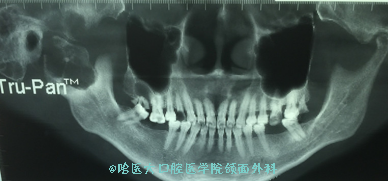

接受手术的是一名45岁的聋哑女性患者,因“右面膨隆两月余”。由家属发现并携其前来我院求治。经门诊拍摄CBCT检查后,发现患者右侧颞下颌关节膨隆,内呈分房样影像,占位累及右侧颧弓,向上内界限欠清。入院经完善检查后,吴衍昌教授团队邀请神经外科杨孔宾教授详细分析了患者病情,完善手术设计,在充分完善术前准备并制定手术方案后,经科室主任焦晓辉教授主持口腔颌面科及相关科室专家对拟行手术方案予以充分的论证并提出了相应的修改建议。术中设计颞-颌后入路手术切口,翻瓣显露肿物后,见其大部居于右髁状突,累及右侧颧弓,颞骨。故于正常骨组织内截断右侧颧弓,解剖剥离面神经总干及诸支,并由颞面干及颈面干间入路于正常骨组织内截断下颌升支,锐性截断其周围肌肉附丽后,将右侧髁状突及肿物一并切除。于颞骨骨损部制备骨窗,沿硬膜水平剥离肿物至颅中窝底,将颅内段肿物完整摘除,充分止血后,按术前设计转移颞肌筋膜瓣填充死腔,关闭手术切口。术程顺利,患者安返病房。

1 右侧髁状突占位,侵袭颧弓,向上内界限欠清